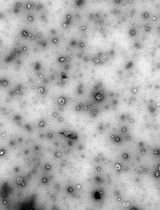

D. Optical microscopy and determination of emulsion microgel sizes

1. Measure the diameters of the emulsion microgels using the optical images of the samples.

Obtain optical images of emulsion microgels with the Olympus I × 73 inverted microscope and a 40× objective.

4. Measure the diameters of the emulsion microgel particles with the optical images obtained in the previous step using measurement tools of the ImageJ software.

5. For the calculation of the average diameter of the emulsion microgel, at least 100 measurements and 10 images for each sample are analyzed. Present the average diameter of particles as mean ± standard deviation.

6. In our case, the microgels were predominantly composed of particles with an average diameter of 2.2 ± 0.3 μm.

Calculation of droplet size of emulsion microgels

To determine the mean size of emulsion droplets, at least 100 measurements were taken with the use of 10 images per sample. ImageJ software was used for image processing and data analysis. First, an optical image of the emulsion microgel was imported into the ImageJ program. Next, the image scale was calibrated in terms of length. Then, using the linear measurement tools available within the program, the diameter of each emulsion droplet was measured directly on the image. Based on the 100 measurements, the average particle diameter and standard deviation were calculated using statistical methods in Excel. Data should be presented as the mean ± standard deviation. Considering the 5% WPI concentration and the 1:3 WPI solution to oil ratio used in the microgels synthesis, we expect the average size of the microgels to be approximately 3.5 ± 0.2 μm. To compare the average particle sizes of different types of emulsion microgels, ANOVA can be used. If the p-value is less than 0.05, the differences are considered statistically significant. To ensure the reproducibility of data analysis and to make it more transparent, we have identified outliers using Grubbs' test statistical method.